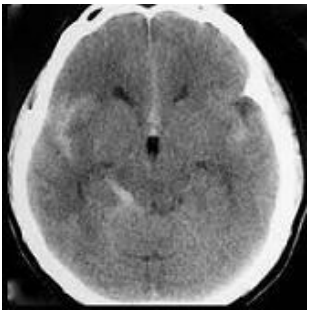

Homem, 33 anos, atleta, apresentando mal estar após cefaléia súbita intensa (escore 8/10) durante prática de salto com vara. Foi trazido ao pronto socorro por sua equipe, já recuperado do mal estar, porém com desorientação temporo-espacial e leve rigidez de nuca. Negavam trauma cranioencefálico. Os exames laboratoriais não demonstraram nenhuma alteração. Submetido a tomografia de crânio que demonstra hemorragia subaracnóidea (HSA) (figura 2).

Figura 2 Tomografia de crânio